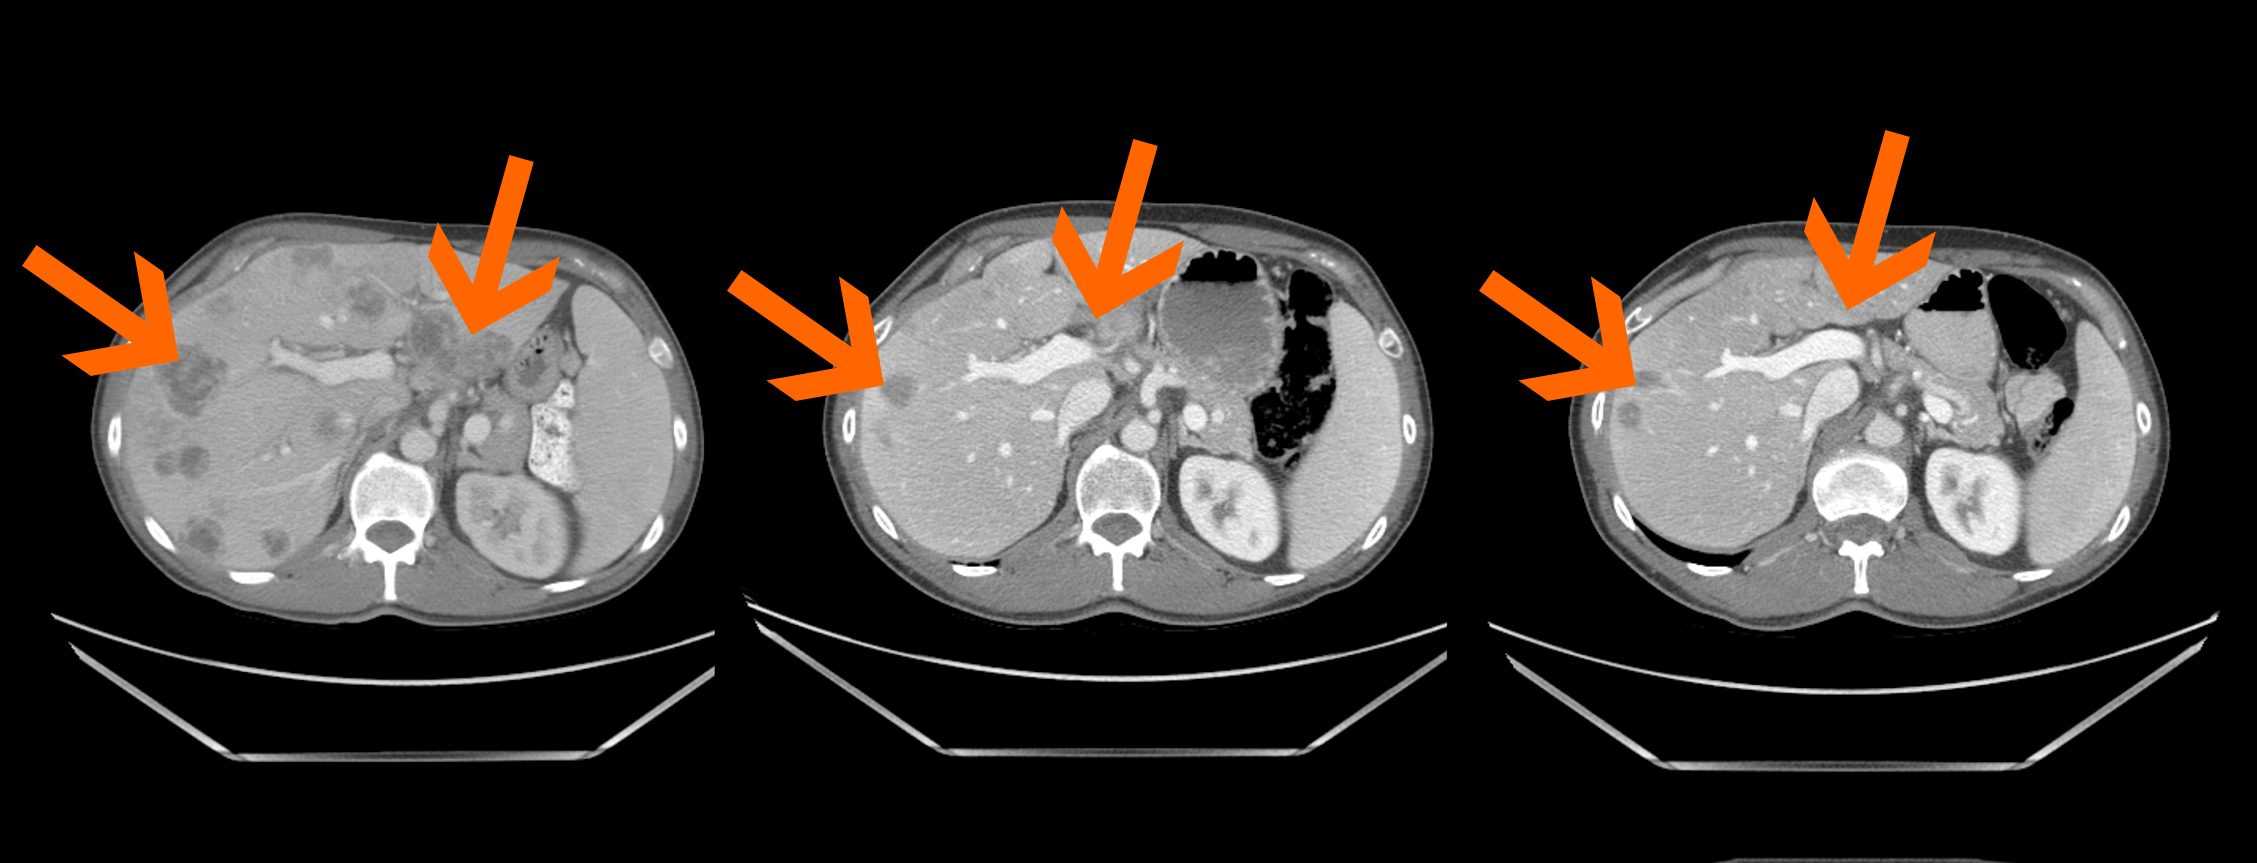

Las mutaciones del RAS y las metástasis en el hígado por cáncer colorrectal